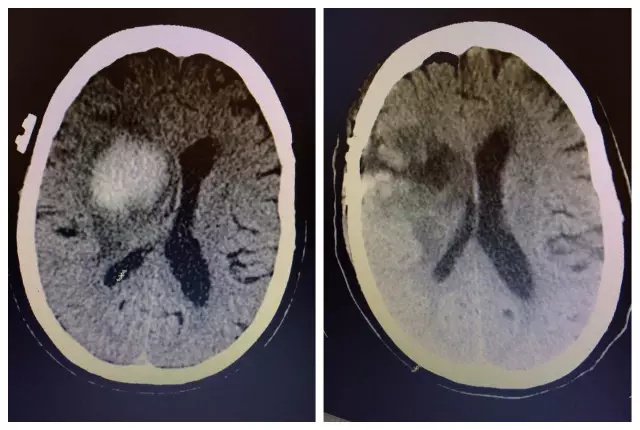

惠州市民周阿姨現(xiàn)年60歲,因意識(shí)障礙4小時(shí)入住我院神經(jīng)外科,既往有高血壓及糖尿病史,CT顯示右側(cè)放射冠-基底節(jié)區(qū)腦出血并破入腦室系統(tǒng),腦出血量達(dá)30ml。起病以來(lái),患者精神差,頭痛明顯,左側(cè)肢體偏癱,生活完全不能自理。

術(shù)前CT和術(shù)后CT對(duì)比

對(duì)于手術(shù)治療,家屬一直心存疑慮,經(jīng)過(guò)醫(yī)生不厭其煩地講解病情后才同意手術(shù)??紤]到患者年齡大,血腫位置深,主刀醫(yī)生文世宏主任率先采用微球囊及內(nèi)鏡輔助為其進(jìn)行了血腫清除術(shù),手術(shù)獲得圓滿成功,血腫完全消失,術(shù)后患者精神明顯好轉(zhuǎn),頭痛消失,肢體活動(dòng)也有了明顯的改善,進(jìn)一步康復(fù)有望生活完全自理。家屬對(duì)手術(shù)效果十分滿意,夸贊這個(gè)手術(shù)真是太神奇了?。?!